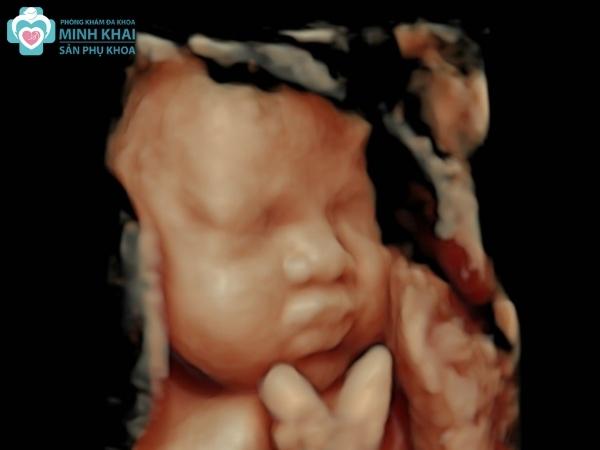

Hình ảnh siêu âm 3D thai nhi tuần 20-25

Vào thời điểm giữa thai kỳ tại tuần 20 đến 25, hình ảnh siêu âm 3D cho thấy rõ hình thái cũng như cấu tạo hộp sọ em bé. Ngoài ra những bộ phận cơ thể khác như tứ chi, khuôn mặt, tim phổi, dạ dày,.... cũng được phản ánh vô cùng chi tiết. Nhờ đó, bác sĩ có thể sớm chẩn đoán bệnh lý cũng như phát hiện khiếm khuyết bẩm sinh cho bé nhanh chóng.